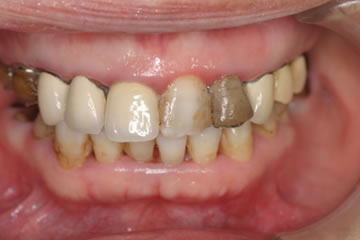

下のレントゲンと口腔内写真は先日インプラント治療が終わった患者さんの初診時です。

いままで仕事が忙しく、口内清掃が不良で歯が喪失していました。

仕事をリタイヤし、これからの人生を快適に過ごすため口腔内をしっかり治したいので来院されました。

Before

歯石の沈着、プラークコントロール不良で、歯肉の発赤がみられます。

奥歯は歯周病、虫歯を放置していたため歯が喪失しています。